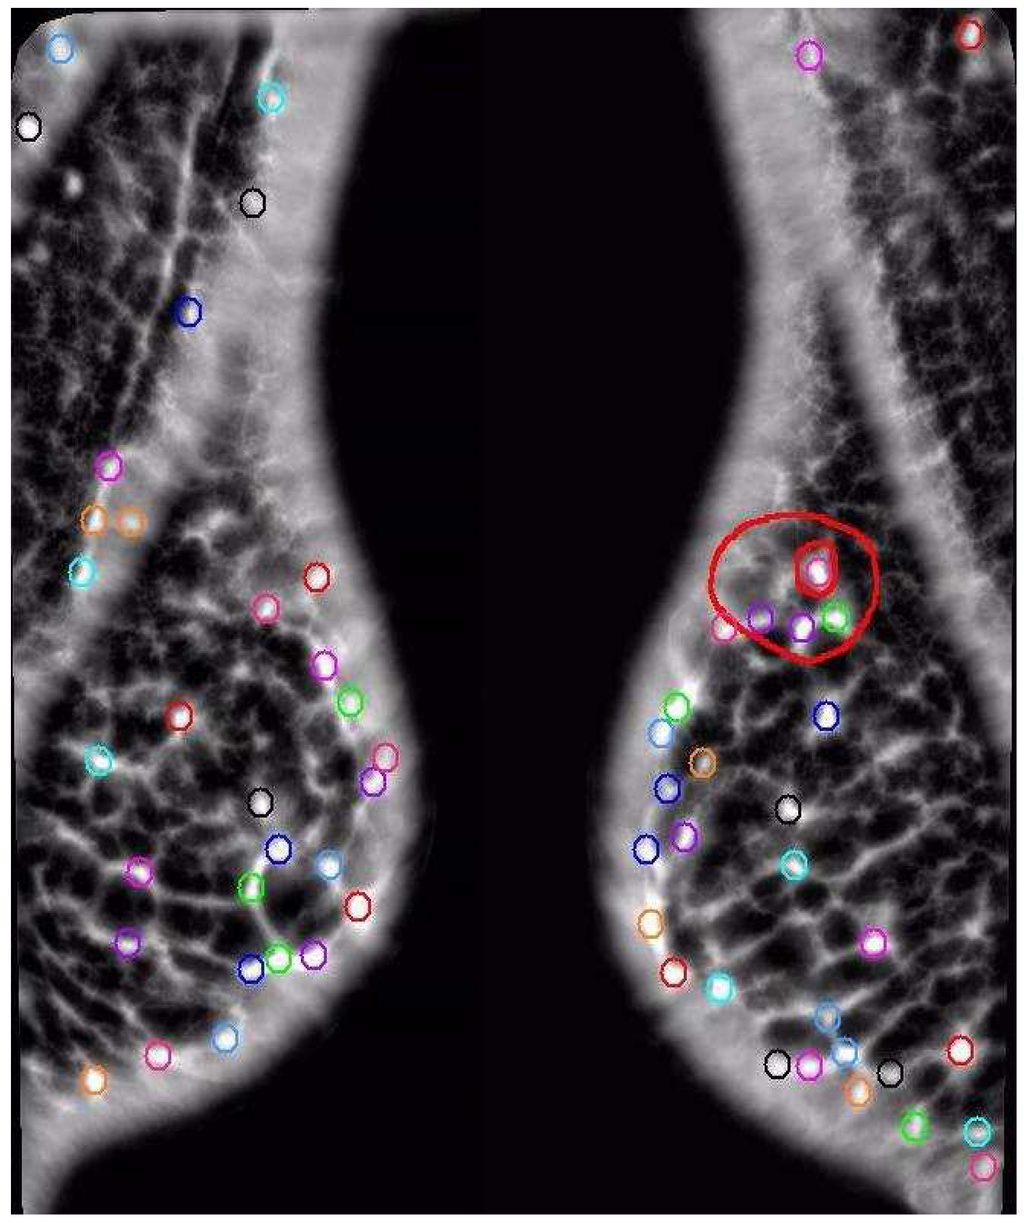

Figure 8. Small Cluster Analysis, a different modeling approach. The AFUM features are the small circles, with the circles on the left coming from the image of the left breast and the circles on the right coming from the image of the right breast. The small clusters are the larger blue circles. This method searches for small clumps of suspicious points and then assigns a cluster there, comparing the number of clusters in the two images, which is a significantly different approach than the one shown in Figure 6 or Figure 7. This method learns the best size for a cluster on the training data. The performance of this approach relative to the other methods showed that AFUM feature clumping was too hindered by the false positive clusters near the breast boundary. This approach may be improved by automatically removing clusters too near the breast boundary.

A different approach explored the importance of the distribution of AFUM feature points, as explored with approaches one through five, versus the clumping of AFUM features together. This sixth approach does not set the number of clusters arbitrarily, but instead learns the number of clusters from the data and learns the best parameterization of the clusters. This image comparisons search for small clumps of AFUM features and then assign a cluster there, as shown in Figure 8, and is called the “small cluster analysis.” The maximum distance between feature points and the minimum features needed to define a cluster are learned on the training set. The clusters were also defined to be centered on a suspicious point because we believed that small clumps of suspicious points tended to form around the central cancer. This assumption may be incorrect, and freeing the cluster centers from that constraint may improve the performance. Exact registration is avoided again by registering the clusters instead of the image or the suspicious points. Comparing the number of clusters in the right image versus the number of clusters in the left image provides a first cut at registering the clusters since a difference in the numbers of clusters implies that some clusters cannot be registered. Improving the cluster registration may improve the performance of the method. This image comparison was motivated by the data, where we observed a small volume of suspicious points at a cancer sites.